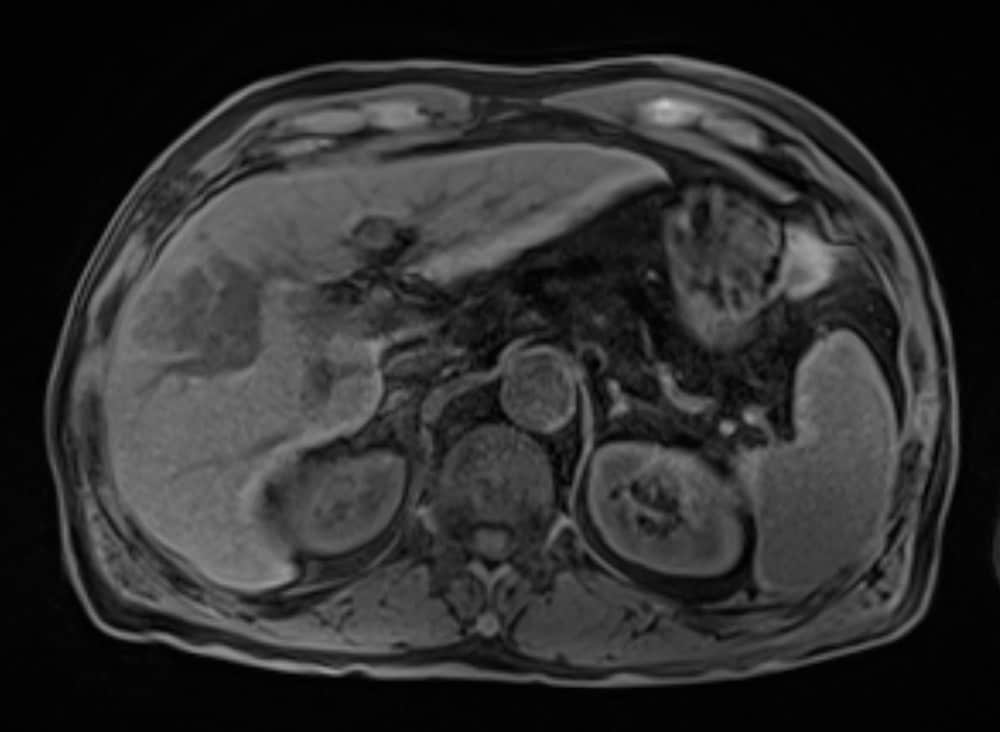

60歳代、男性、57kg、肝細胞癌

前医よりB型慢性肝炎に対して核酸アナログ投与し定期フォローを継続されていた.AFP上昇,腹部USでの画像異常を指摘され精査加療目的に当院紹介受診となり,EOB-MRIを施行した.

EOB-MRIの結果から門脈本幹までの腫瘍栓を伴う肝細胞癌と診断した.EOB-MRI肝細胞相で不均一高信号を呈する病変ではなく,均一低信号を呈しており複合免疫療法が奏効する可能性があると考えられた.Vp4の門脈腫瘍栓を伴う切除不能進行肝癌に対し複合免疫療法(Atezolizumab/Bevacizumab併用療法)を開始した.4コース終了後には門脈腫瘍栓一部残存を認めるも肝腫瘤は著明に縮小し,5コース終了後に根治切除術(肝右葉切除術+門脈血栓除去術)を施行した.術後は薬物療法の再開なく現在までの約14ヶ月無再発で経過観察継続中である.

本症例におけるEOB・プリモビスト造影MRIの役割について

EOB-MRIで門脈腫瘍栓を伴う肝細胞癌であること,不均一高信号を呈する病変で無いことを確認し複合免疫療法(Atezolizumab/Bevacizumab併用療法)を開始した.EOB-MRI肝細胞相は肝細胞癌におけるWnt/βカテニン変異のイメージングバイオマーカーとなることが知られており(Ueno A et al. J Hepatol 61:1080-1087,2014),不均一高信号な病変は複合免疫療法の治療効果が乏しい可能性が指摘されている(Sasaki et al. Cancers,14,827,2022).必ずしも治療奏効を保障するものでは無いが,本症例では肝細胞相で均一低信号を呈しており,複合免疫療法の治療効果が期待される症例であった.